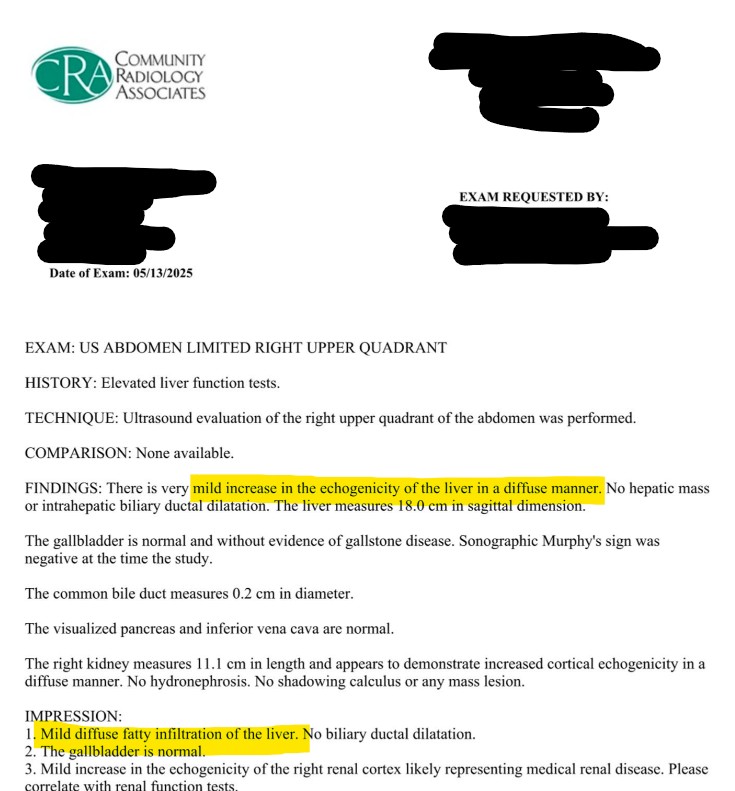

My Ultrasound Results:

Don’t let the word ‘mild’ fool you. In medical terms, ‘mild’ just means I don’t have cirrhosis yet. But looking at the data, my liver was 18c, significantly enlarged. Even though I had a normal BMI and ‘looked fine,’ my liver was inflamed and swollen. This was the wake-up call.

Note: The ultrasound report also noted some echogenicity in my kidneys, which my nephrologist cleared as non-threatening, but it highlights that metabolic stress affects the whole system, not just the liver.